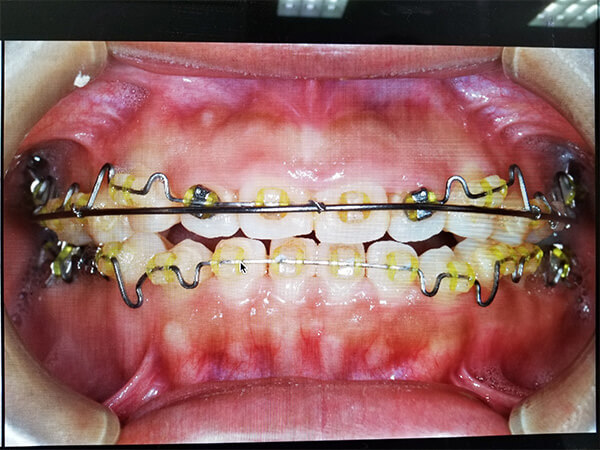

私事ではありますが、今年の4月から矯正を始めました!

途中経過ではありますが、4月と現在の写真をアップさせていただきました。